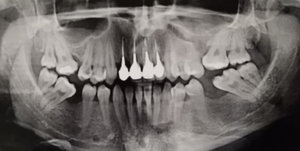

Около 3-х лет назад мне удалили нервы из верхней правой шестерки. Спустя 2 года воспалились корни, т.е. около 9 месяцев назад перелечивали корни, поставили коронку. Месяц назад зуб снова заболел, оказалось воспаление под корнем.

Хотелось бы узнать, действительно ли есть воспаление? И вообще в целом ситуацию насчет этого зуба, какое лечение следует предпринять? Есть 2 панорамных снимка.

Действительно, в зубе имеется хронический воспалительный процесс, причина — некачественное лечение каналов. Зуб будет лечиться в несколько посещений, и при квалифицированном подходе его вполне можно спасти.